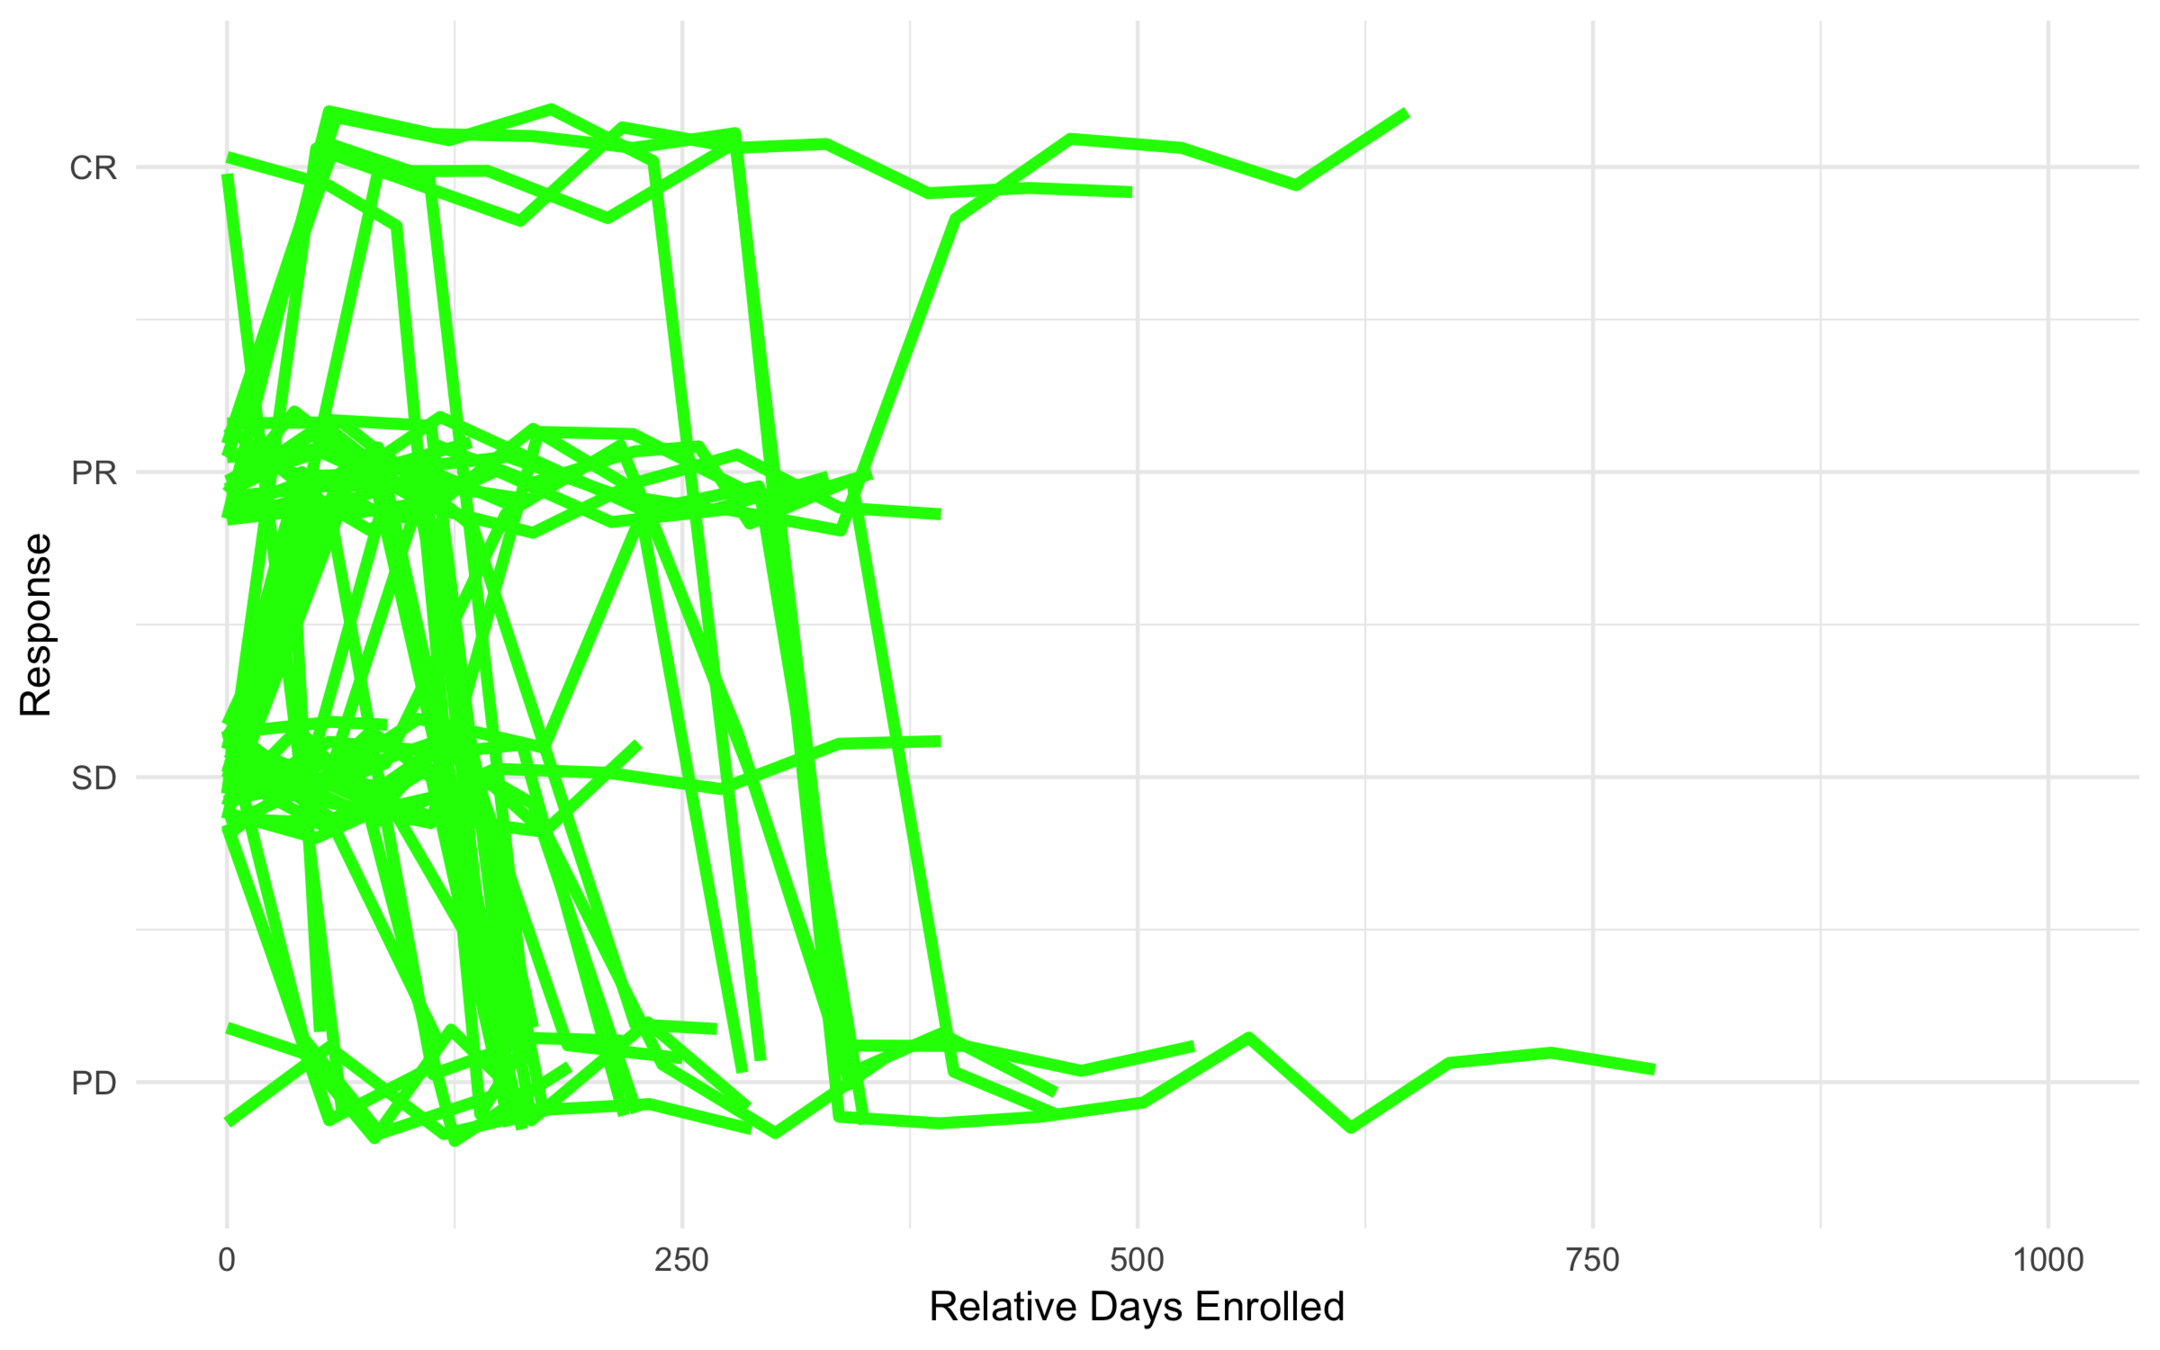

All Trajectories

Low Risk

Intermediate Risk

High Risk

Anonymous Drug 1

Was found to be effective for a certain type of cancer.

Ran into problems with severe toxicity events (449 toxicities out of 607).

Goal was to find subtypes least (or most) likely to have toxicity events.